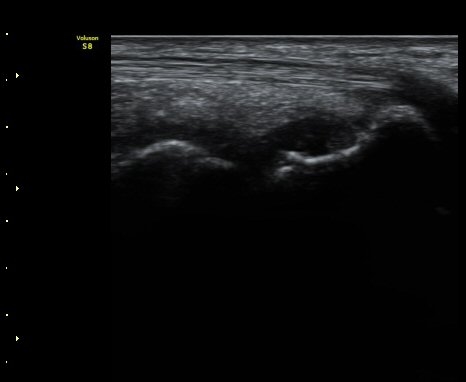

ÃÊÀ½ÆÄ °Ë»ç

¼Õ¸ñÀÇ Á¾´Ü

ÁÖ»ó°ñ ¼±»ó°ñÀýÀº ´Ü¼ø¹æ»ç¼± ÃÔ¿µ ½Ã È®ÀεÇÁö ¾ÊÀº °æ¿ì°¡ ¸¹Àºµ¥ ÀÌ ¶§ ÃÊÀ½ÆÄ

°Ë»ç°¡ ÁÖ»ó°ñ °ñÀý Áø´Ü¿¡ ¸Å¿ì À¯¿ëÇÏ´Ù. ±×·¯¹Ç·Î ¼Õ¸ñ ´ÙÄ£ ÈÄ Áö¼ÓÀûÀÎ ÅëÁõÀ»

È£¼ÒÇϰí ÁÖ»ó°ñ ºÎÀ§ ¾ÐÅëÀ» º¸ÀÌ´Â °æ¿ì ÃÊÀ½ÆÄ°Ë»ç¸¦ ½ÃÇàÇÏ¿© ÁÖ»ó°ñ °ñÀý ¿©ºÎ¸¦

È®ÀÎÇØ¾ß ÇÑ´Ù.